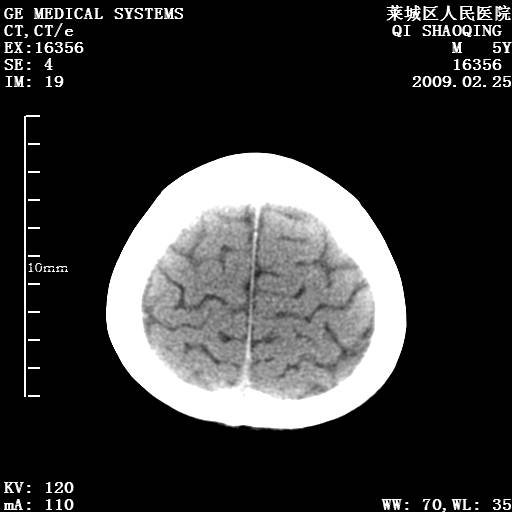

以下是引用wangzhengyuan在2009-2-28 10:22:00的发言:[br]甲状旁腺功能减退引起的脑改变.

以下是引用zsl6918在2009-2-28 10:17:00的发言:[br]首先考虑甲状旁腺功能低下所致,可结合实验室检查明确.另外需除外先天性宫内感染所致.

以下是引用余辉在2009-3-1 9:35:00的发言:[br]患者明显的肢体及智力改变,不支持fahr病,多考虑甲旁低,有可能伴有甲低(呆小症).进一步检查。